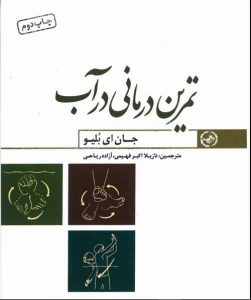

کتاب تمرین درمانی در آب از سری فایل های آموزشی انجمن دیستروفی ایران

نوشته جان ای بلیو، ترجمه از نازیلا اکبرفهیمی و آزاده ریاحی.